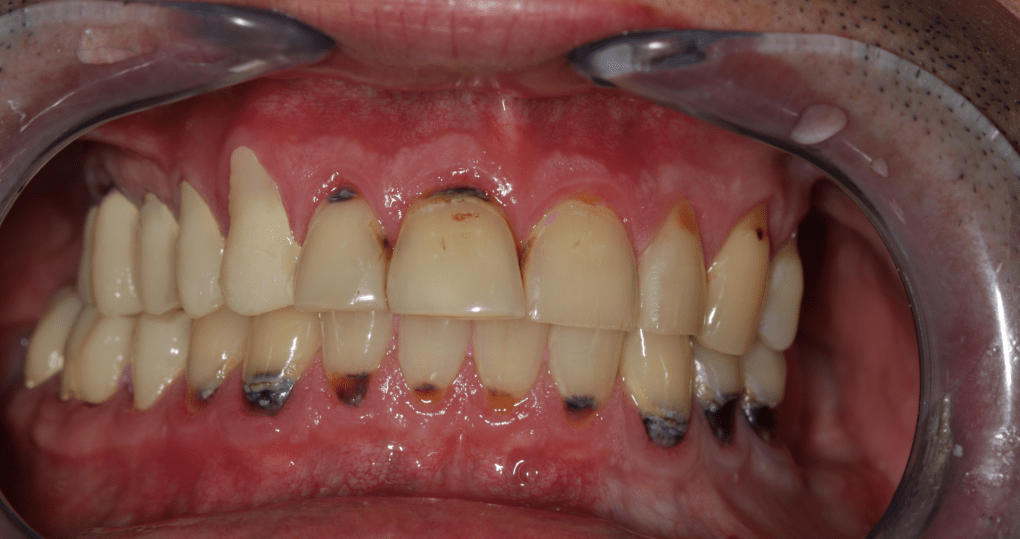

Páciensünk azért kereste fel fogászatunkat, mert évek óta állkapocsízületi problémákkal küzdött, melyek miatt fogai ápolását is elhanyagolta. Első találkozásunkkor szájnyitási nehézségekre, szimmetrikus állkapocsízületi kattogásra és éjszakai parafunkciós mozgásokra (csikorgatás, szorítás) panaszkodott, melyek megnehezítik mindennapjait.

Klinikai és radiológiai vizsgálatok alapján megállapítottam, hogy a túlterhelés (parafunkciók) jelei látszódnak a fogain is: abfrakciók – nyaki kopások és attríciók –, rágófelszíni kopások is kifejezettek voltak. Harapása igen bizonytalan tartományban mozgott, nem volt egy stabil helyzet, amelybe határozottan össze tudott volna zárni (csak kereste a megfelelő pozíciót.) TMI-vizsgálat során reciprok crepitációt (kattanás nyitáskor-záráskor is), myofascialis eltéréseket (hypertrófiás musculus masseter – túlterhelt rágóizom) és beszűkült mozgáspályákat találtam. Emellett sajnos a nem megfelelő szájhigiénés szokások miatt a fognyakak „sérült” részein szuvasodások is megjelentek, illetve a bal alsó hatos és a jobb felső hetes fog már oly mértékben destruálódott, hogy el kellett távolítani őket.